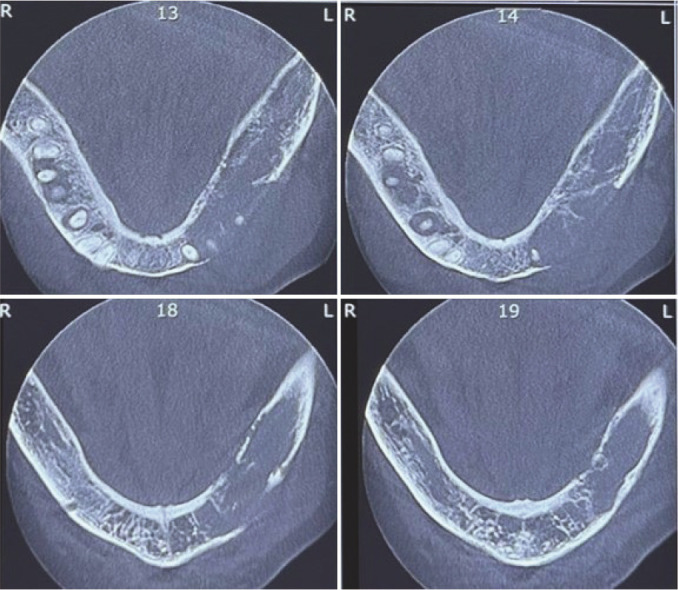

Jawbone metastatic lesions are a diagnostic challenge because of their rarity and variable clinical, radiographic, and histopathologic characteristics. This paper presents a 57-year-old female with a chief complaint of lower face swelling. Cone beam computed tomography (CBCT) showed a multilocular radiolucency with right angle septa in the left mandibular area with cortical destruction. She had a history of right breast cancer about six years ago. Histopathologic examination revealed sheets of malignant small round cells. Immunohistochemistry (IHC) was only positive for cytokeratin (CK) and GATA3. CA15-3 tumor marker was higher than the normal range. Based on the aforementioned data, the diagnosis of metastatic breast carcinoma was performed. The whole-body and computed tomography (CT) scan showed just involvement in the left mandibular area. The radiographic appearance of metastatic lesions might be misleading, and microscopic sections might be poorly differentiated, therefore, a precise past medical history, IHC staining, and tumor markers are valuable issues in diagnosing oral cavity metastasis.